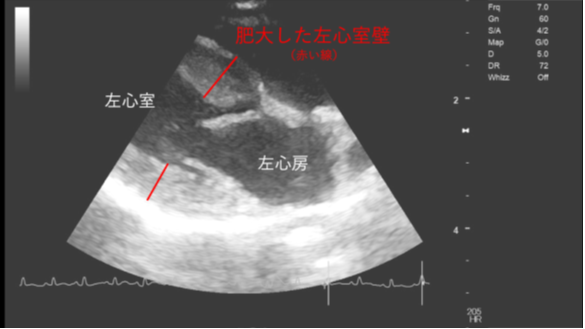

ねこちゃんで発生の多い心臓病は、「心筋症」です。

「心筋症」とは、心臓の筋肉「心筋」が分厚く肥大化する病態です。

肥大化した心筋の場所により病態は変化します。